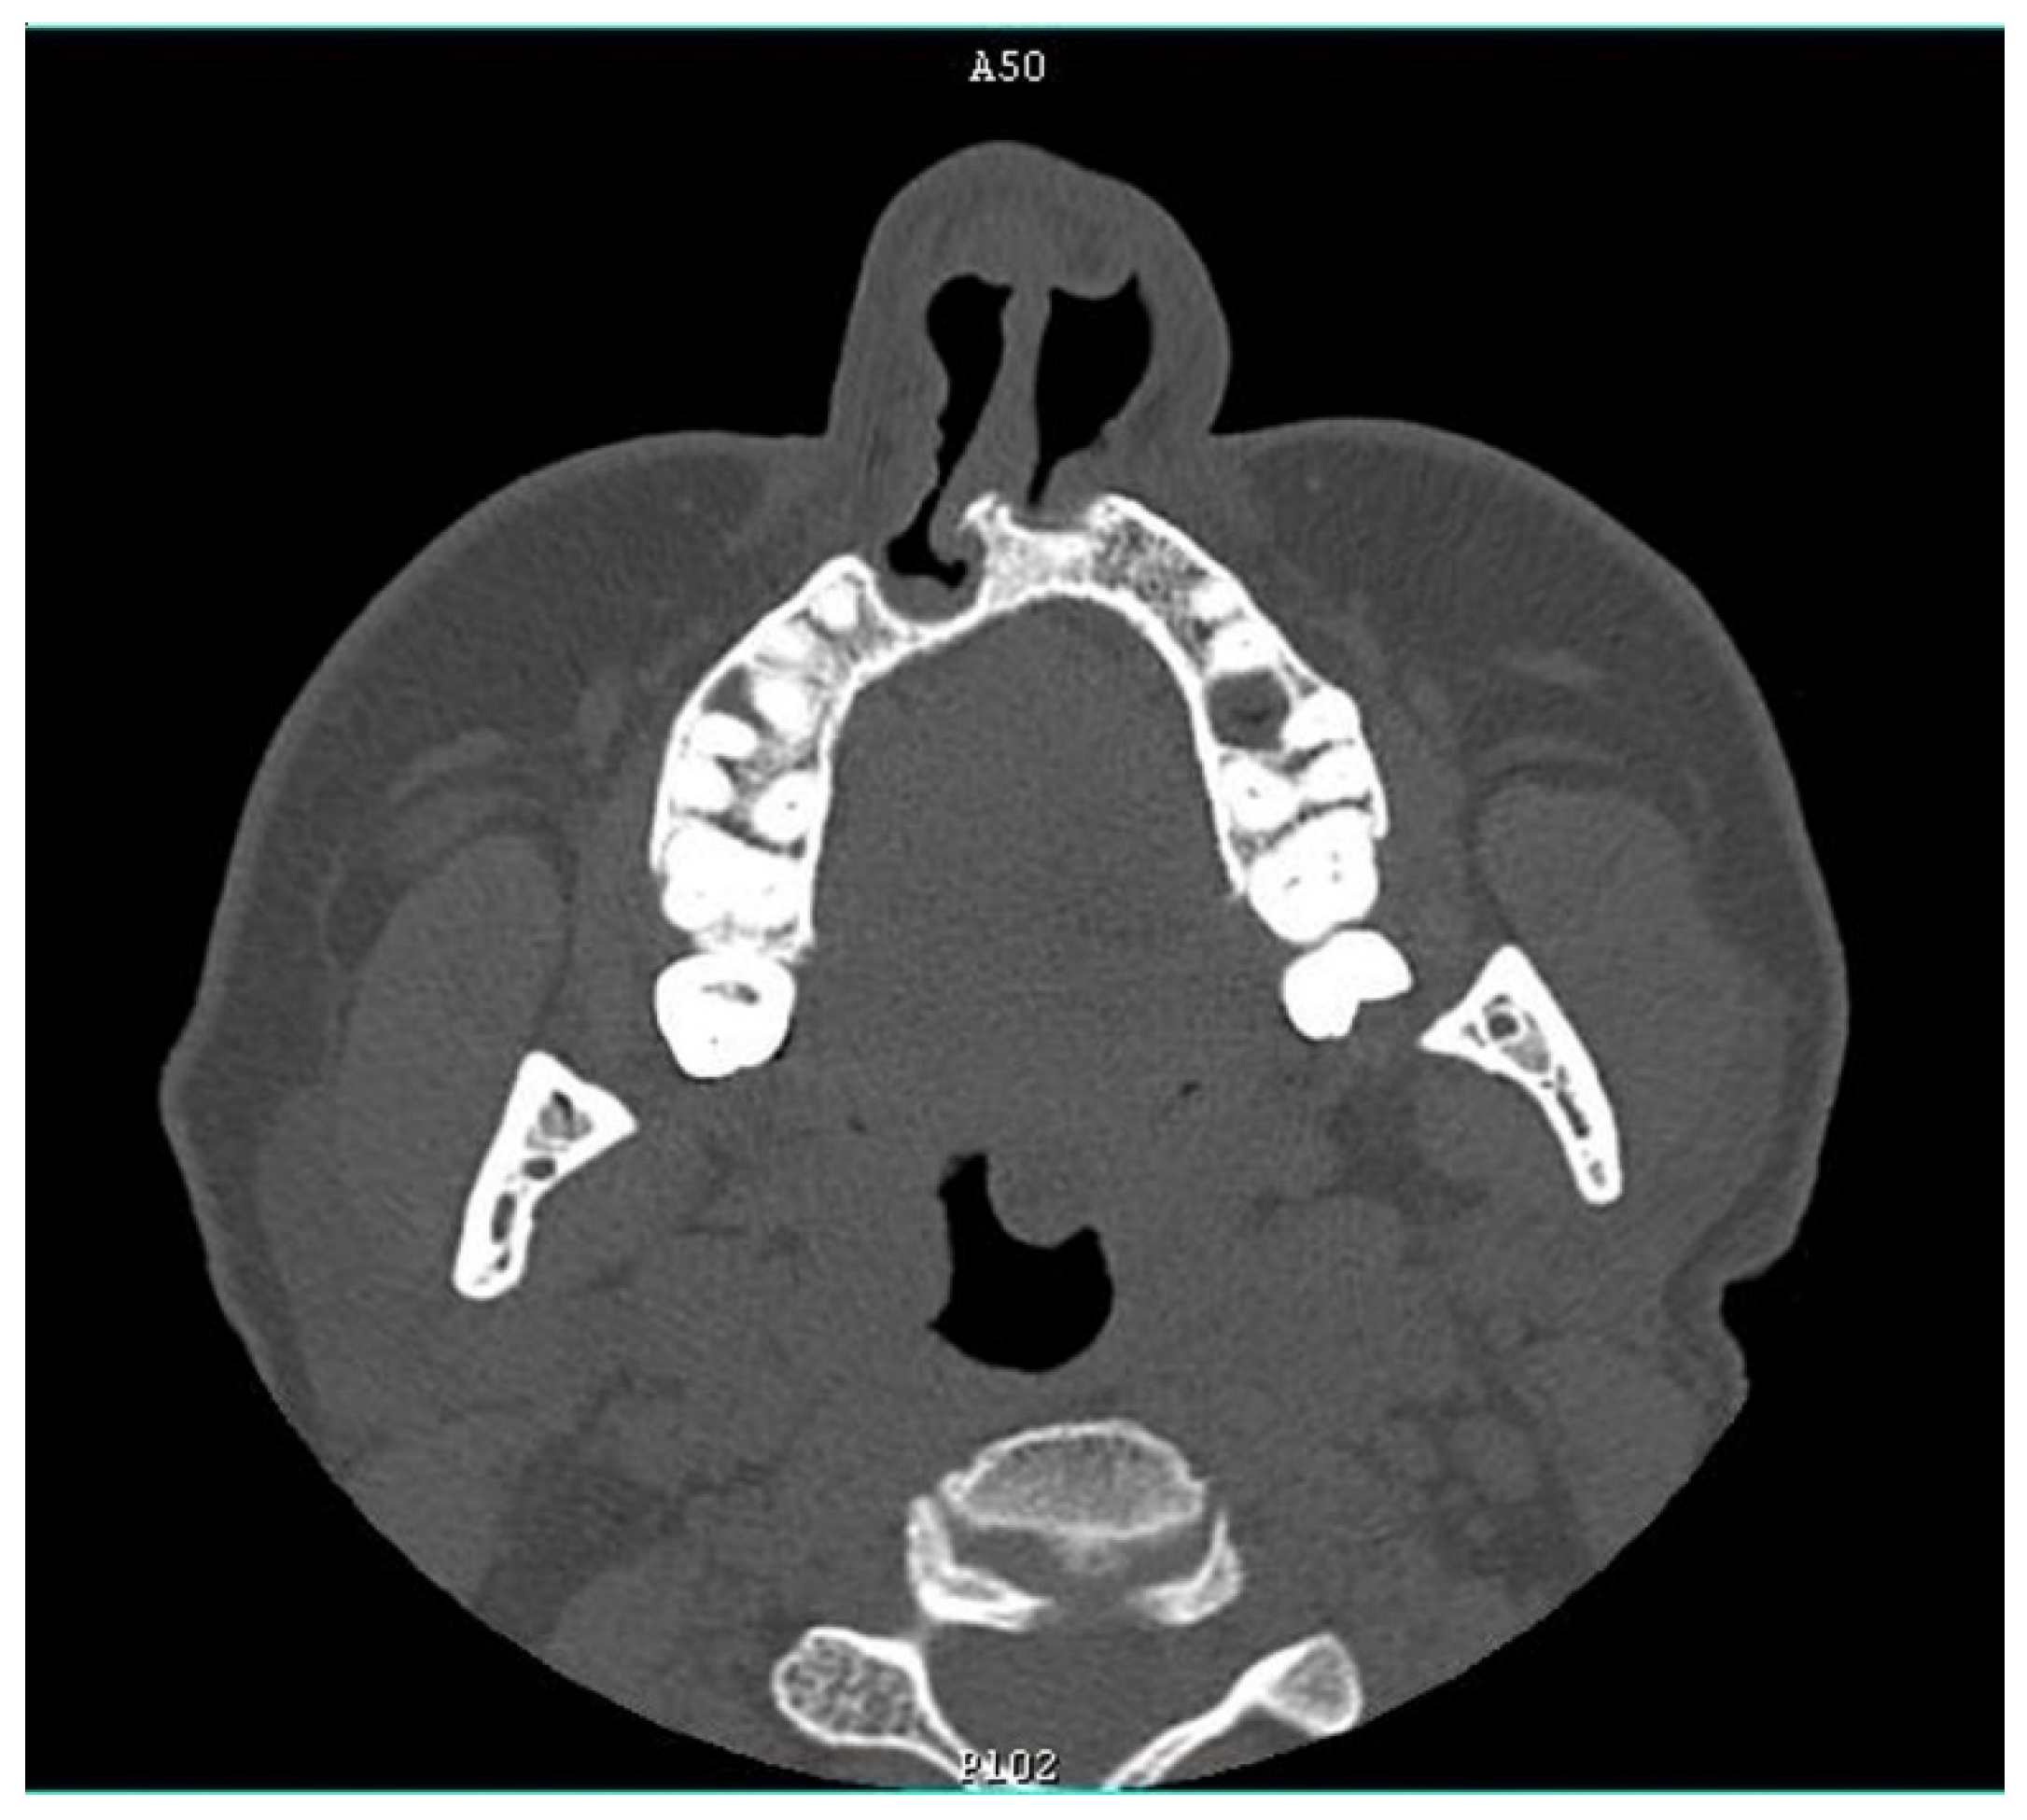

At the age of 3 years, she was hospitalized in the pediatric cardiology department due to a sudden deterioration of her general health. A chest X-ray revealed an increased blood flow through the lungs with symptoms of pulmonary hypertension and an enlarged heart, especially the right ventricle, and a wide mediastinum. A heart catheterization showed APW with a significantly increased pulmonary resistance limiting the left–right shunt through the window, an enlarged left atrium and left ventricle with a preserved systolic function. A physical examination revealed a holosystolic crescendo–decrescendo murmur with the crescendo peak closer to the first heart sound, a high amplitude, split second heart sound over the pulmonary artery (PA) and protosystolic murmur over PA and at the Erb point. The child underwent a total correction of the heart defect in extracorporeal circulation. An aortotomy was performed and the pulmonary artery was cut with a longitudinal APW closure (with a velour patch). One month after the surgery, a protomesosystolic decrescendo murmur was present in the projection of the pulmonary artery valve, apex and Erb point. In an ECHO, a paradoxical movement of the intraventricular septum was observed and the left ventricle was within the upper limit of the norm. The child was discharged from the department and followed-up with regularly. At the age of 17 years, she was hospitalized in the cardiology department for extended examinations. An ECHO examination showed a pulmonary valve regurgitation (I/II degree), PA with a widened trunk, widened ascending aorta with narrowing at the isthmus level and acceleration of flow, but without features of coarctation. The exercise tolerance test was correct, without signs of hypertrophy and damage to the heart muscle in resting ECG. A twenty-four-hour Holter monitoring also did not show any disturbances.

Figure 4). The patient’s chest X-ray reveled dilated bronchial vessels, and an ECHO examination showed an increased peak velocity of blood in the PA, indicating stenosis (at the level of the APW repair), which was stable and subclinical (

Figure 5). The patient had a healthy female child without any congenital anomalies.